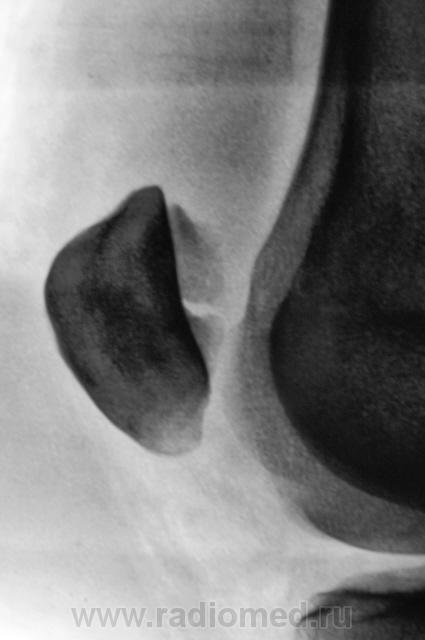

перелом надколенника( редко такой встречается) препателярная гемабурса, гемартроз, сильно пострадала суставная поверхность надколенника

Наверно все таки пателля бипартита. Представить, чтобы так красиво и ровно откололось - трудно... А мягкотканный компонент знатный...

Сам думал о "бипарцита", кстати, недавно был случай с "трипарцита". Но в данном случае был в растерянности, клиника "зашкаливает", конечно, возможно из-за мягкотканного компонента.

В минус травме говорит такая "красивенькая форма" отломка? НО при бипарите про мягкотканный компонент я данных ненашел..